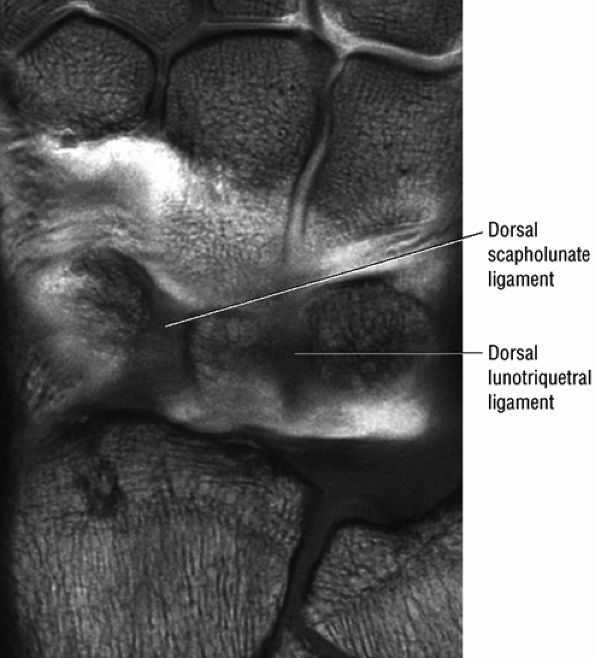

FIGURE 10.3 ● Identification of the dorsal fibers of the scapholunate and lunotriquetral ligaments on a coronal T1-weighted arthrogram. Although MR arthrography is frequently performed with FS, this decreases signal-to-noise. Routine FS PD FSE sequences are still used when performing MR arthrography, usually in the coronal and axial planes, to evaluate muscle and tendon pathology, chondral abnormalities, subchondral marrow edema, and noncommunicating ganglions. Postarthrogram sequences limited to FS T1-weighted sequences alone are inadequate for comprehensive diagnostic assessment.